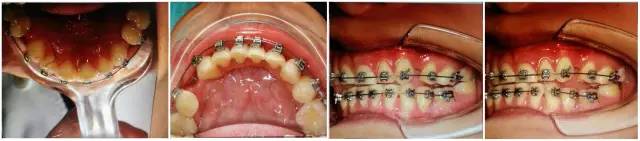

檢查:上前牙松(Ⅱ)°,牙齦紅腫,牙周膜間隙增寬。(如照片所示)

口內(nèi)情況,如以下照片所示: